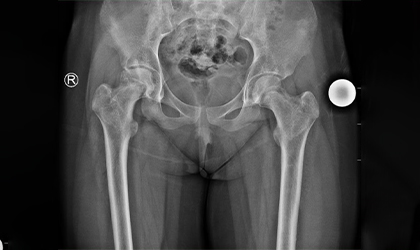

Cancer, Hips, Triumph

This is one of the youngest girls I have done a hip replacement in. Her right hip was replaced at the age of 13,